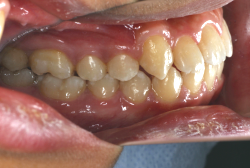

診断の結果、典型的なアングル2級1類の上顎前突です。上下歯列の正中の不一致も見られます。しかし、歯の大きさは平均値に近く、配列の凸凹がそれほど見られません。このまま放置すると、将来的には抜歯を伴う矯正治療を行う可能性が高くなりますが、このタイミングで適切な治療をすると、非抜歯治療が可能かもしれません。

矯正歯科医が着目するのは、奥歯の噛み合わせの位置関係です。前歯の位置にそれなりの差が生じていても、奥歯の位置が正しければそれほど重症という評価にはなりません。このケースの場合は、上下の第一大臼歯の位置関係は、直線的に一致しているタイプでした(矢印が一致)。混合歯列時期の奥歯の位置関係としては、ほぼ正常な状態といえますが、症状から言うと、上の奥歯をもっと後ろに下げてやることができれば、上顎歯列全体に余裕ができるので、凸凹も解消できるし、前歯の傾きを内向きに修正することもできると考えられました。しかしこのまま全体に永久歯が生えきってしまうと、上の前歯が出たままになってしまいますので、生え替わりが完了する前に大急ぎで奥歯を後ろに下げる必要があると判断しました。

こういう症状でもっとも効果があるのが、顎外固定装置と言って、お口の外部から奥歯に力をかける方法です。 写真の装置はネックバンドというタイプの装置です。この装置は取り外し式ですので、夜寝るときに毎日自分で取り付けて、寝ている間に少しずつ上の奥歯を後ろに下げていきます。この装置には、奥歯を後ろに下げる効果だけでなく、上顎の過剰な成長発育の抑制、下顎の成長促進作用があるとされており、上顎前突の症状にはいずれも有利な効果が期待できます。

ネックバンドを1年半使用して、上顎大臼歯が十分後ろに下がったところで、裏側にリンガルアーチという固定のワイヤーを取り付けて、新しく生じた隙間が狭くならないよう「保隙(ほげき)」という処置をして、永久歯が生えそろうまで待機中の様子です。配列全体に隙間が生じているのがお分かりいただけると思います。これだけの隙間が確保できていれば、抜歯をしなくても、あとで上の前歯を内側に理想的な角度で引っ込めることができます。このように完全に永久歯列になる前に、十分な隙間が確保できるかどうかが、非抜歯で矯正できるかどうかの分かれ目になります。

初診時と違い、上の奥歯がより後方に下がっていることが分かります。ただしこの段階では奥歯は後ろに下がりすぎの状態です。しかし次の段階でマルチブラケット法を始めると、上の奥歯は次第に前にズレて来ます。最終段階で正しい位置にするためには、この段階では余分に後ろに下がっている必要があります。

第2段階としてマルチブラケット法を非抜歯で1年間行いました。歯の傾斜が修正され、正中も一致し、美しく機能的な配列に仕上がりました。再診時に確保した隙間をすべて使って、すべての永久歯を理想的な位置に配列することができました。前傾していた上の前歯は真っ直ぐに直立し、完全な正常咬合が確立できています。